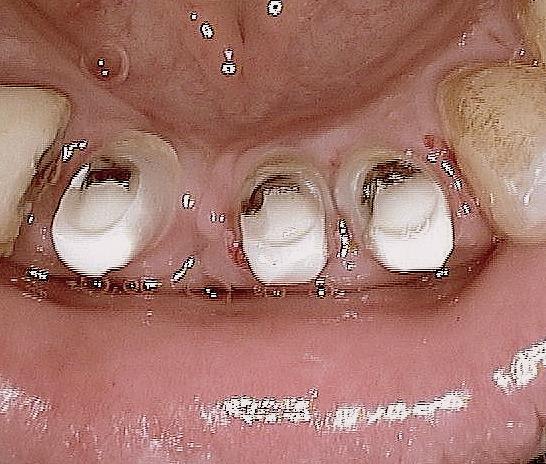

Oui tu as bien raison :-) Ci joint quelques photos en rapport avec ta question ....

20120327 154220 azpc5k - Eugenol

20120327 152704 psin9r - Eugenol

11 immidiat implantation ajhuew - Eugenol